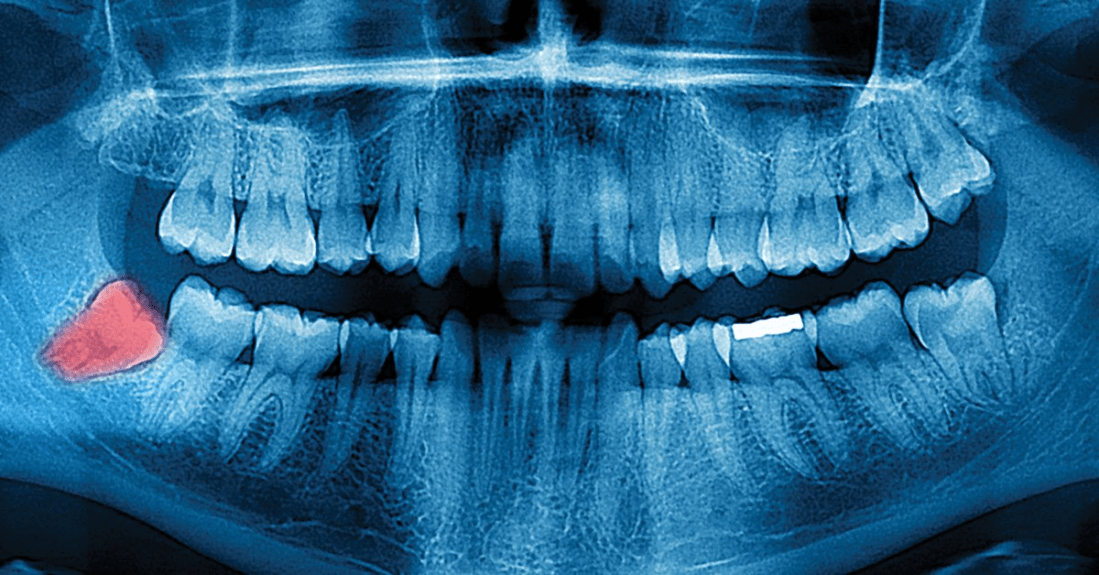

También en nuestro cuerpo han quedado elementos vestigiales para que podamos entender por qué nuestros antepasados, los primeros, lograban vivir tantos años en perfecto estado de salud.